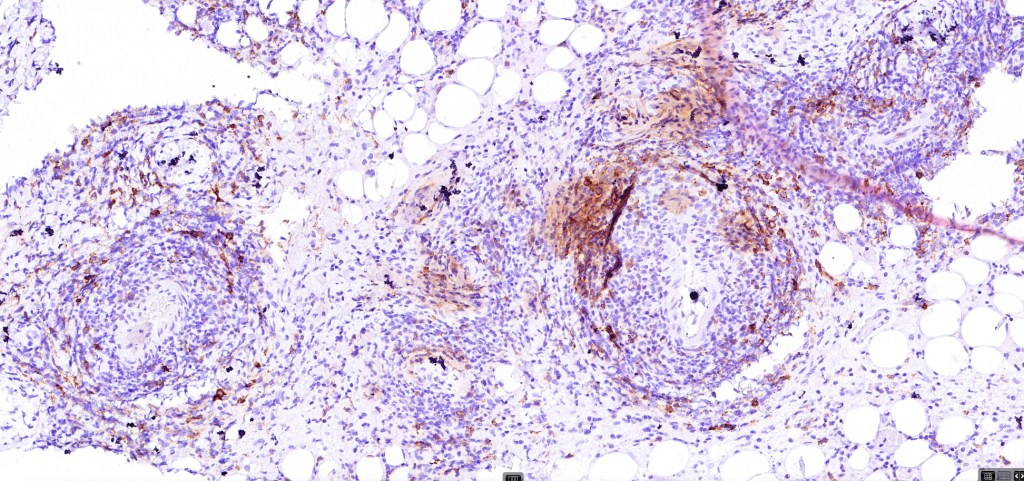

•Type C: 7-10% nodular infiltrate similar to primary cutaneous anaplastic large cell lymphoma

•CD45, CD30 +ve/CD15 –ve (types A & C)